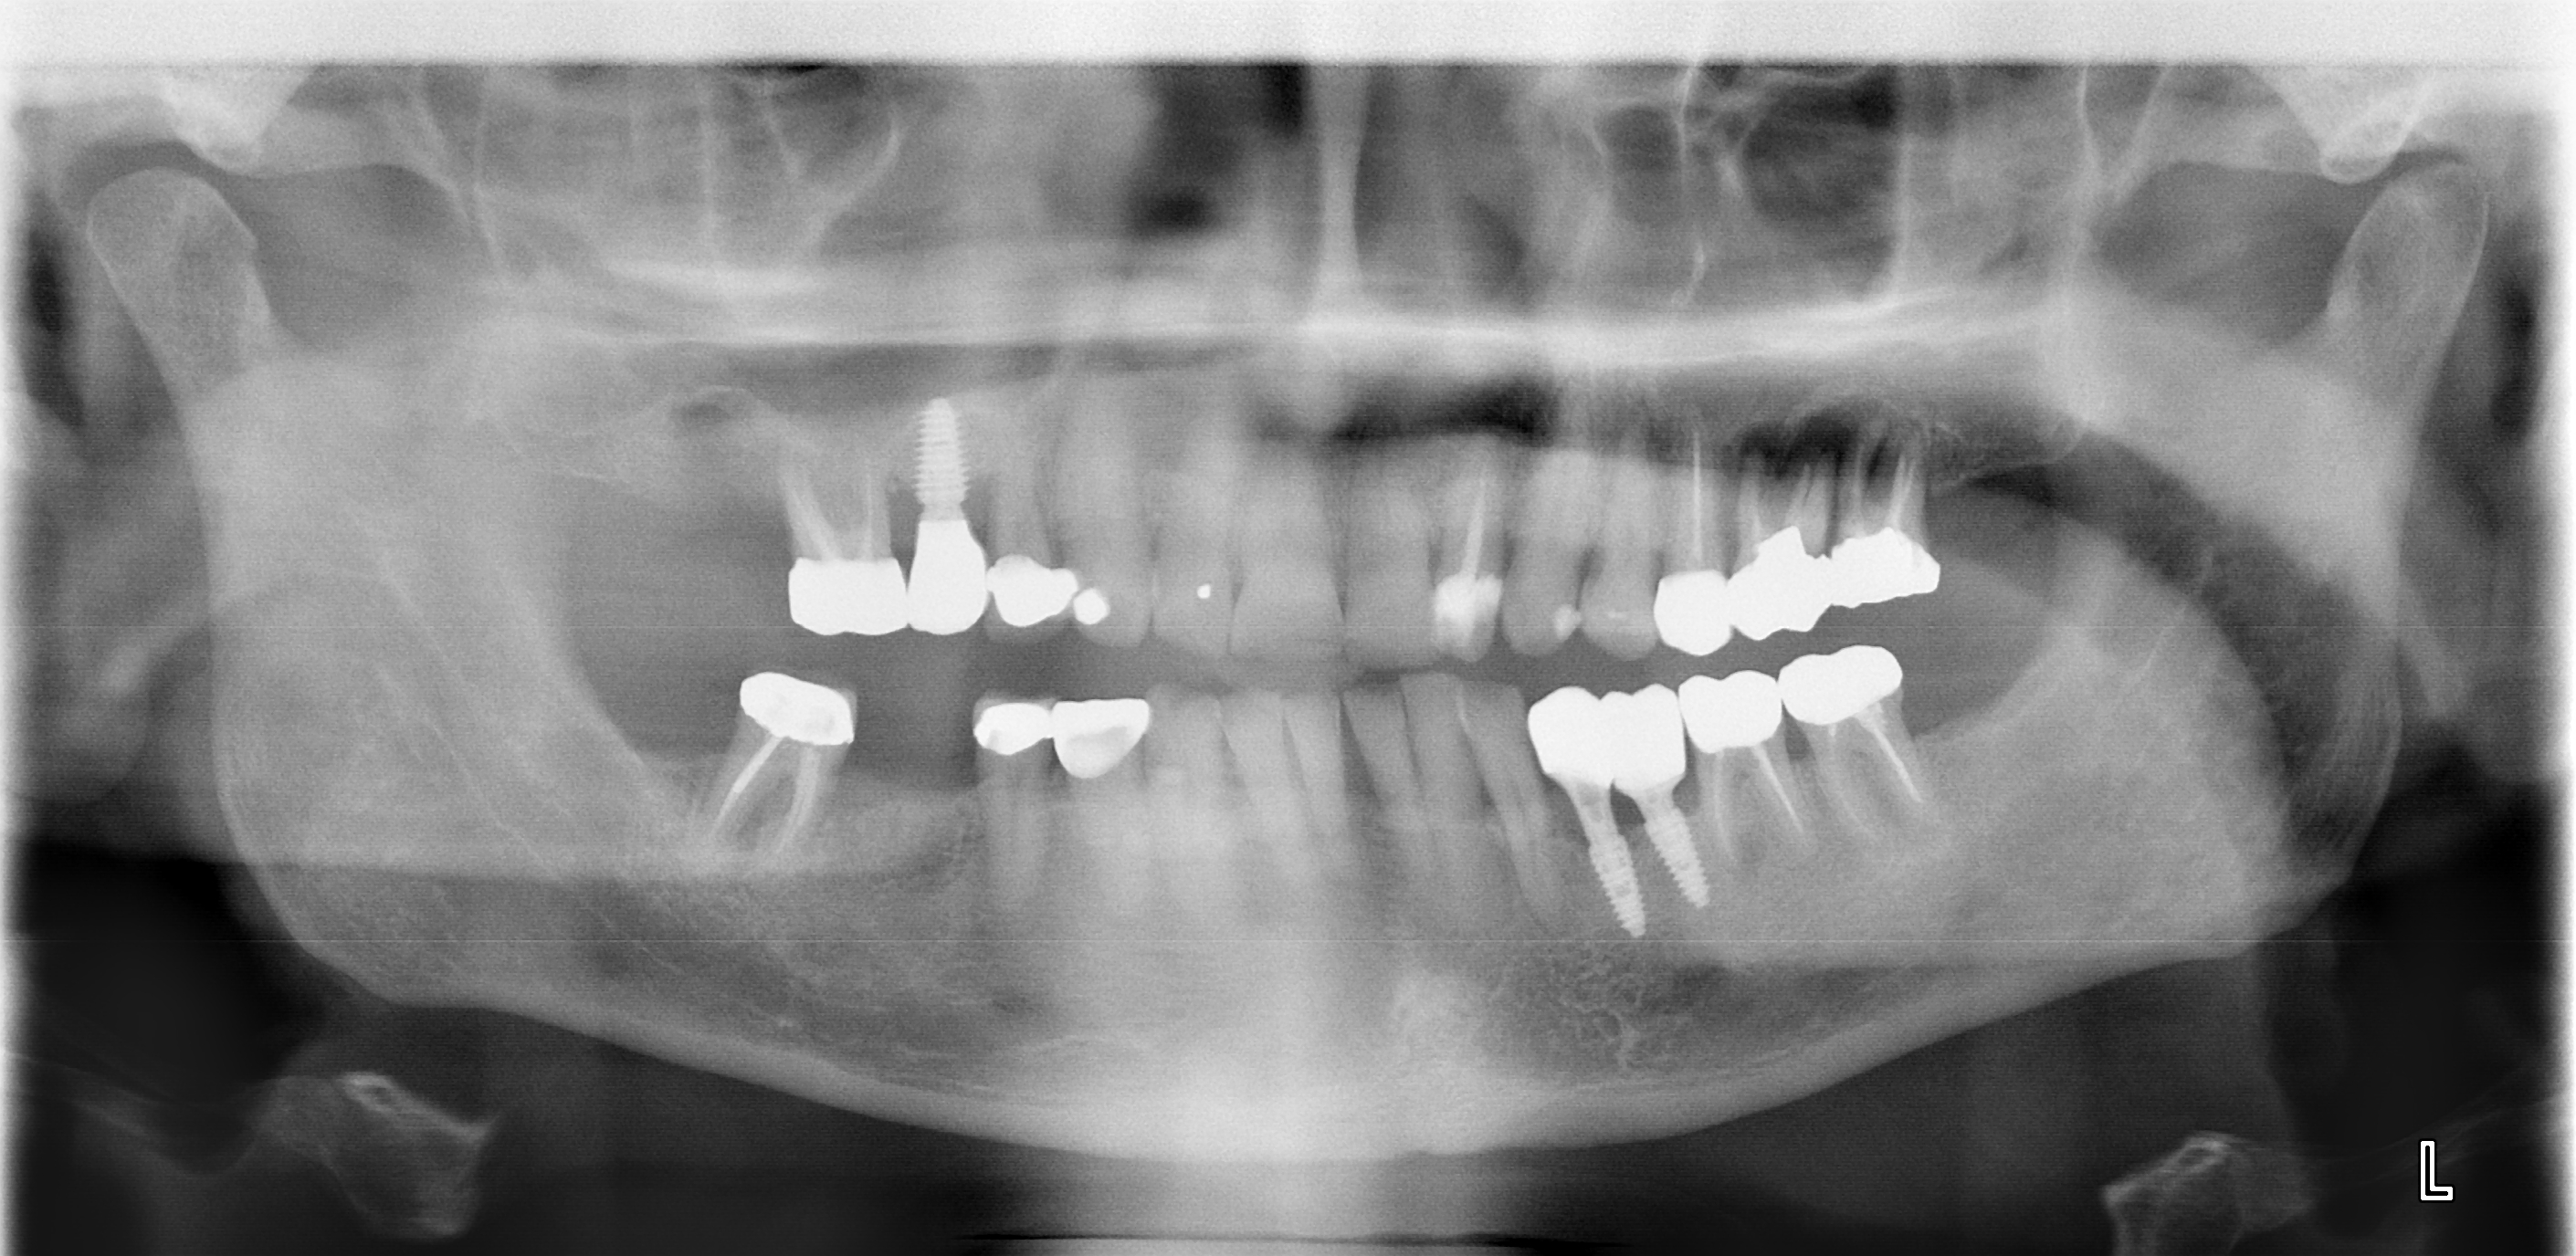

I go the dentist for final fitting of the implant that replaces the molar that was untimely ripped in London earlier this year.